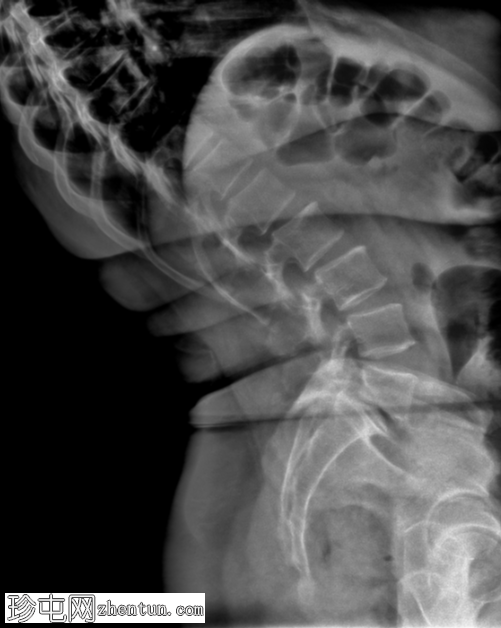

2.png

侧面

3.png

(放大)

L5-S1 椎体II度滑脱。

双侧椎间盘缺损。

L5-S1椎间盘间隙缺失,伴有退行性病变。

脊柱动态成像(屈曲和伸展视图)有助于评估不稳定性,这种不稳定性在退行性脊柱疾病中最为常见。